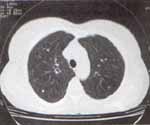

Había recibido en los últimos tres años y medio metotrexate, ácido fólico, colchicina, ASA, omeprazol y verapamilo 240 mg al día en dos dosis desde hace ocho meses por hipertensión arterial. Traía estudios radiológicos pulmonares desde 1998 donde se observaron múltiples opacidades nodulares de 1 a 4 mm de diámetro de densidad cálcica sin encontrar signos de hipertensión pulmonar (Figuras 2 y 3).

Figuras 2 y 3. Estudios radiológicos pulmonares que muestran múltiples opacidades nodulares de 1 a 4 mm de diámetro de densidad cálcica diseminadas en ambos campos pulmonares.